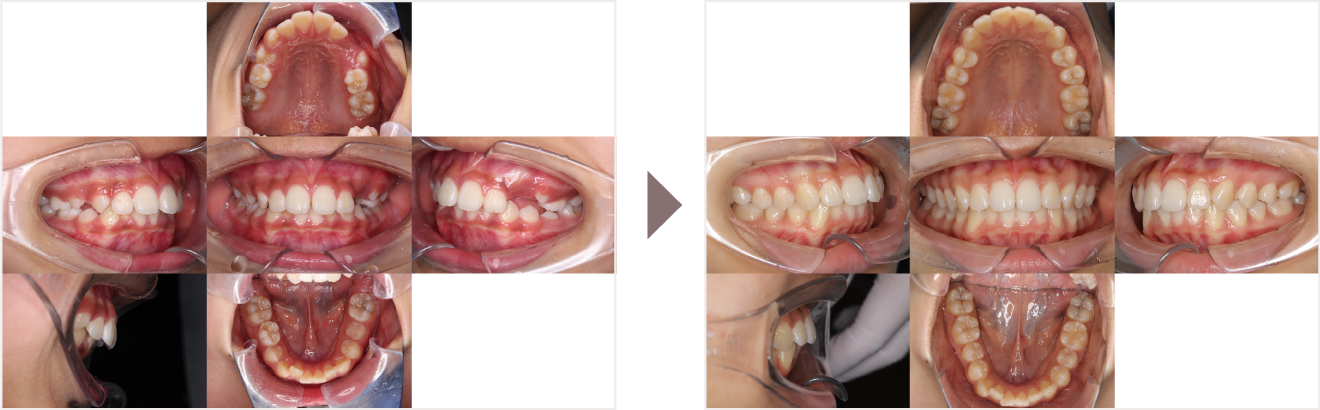

症例叢生

性別

期間8年8ヶ月

治療内容N-Bimler装置、Neo-Capを使用して治療

治療における

副作用・リスク

装着しないと効果は出ません

金額ビムラー装置:550,000円

ネオキャップ:4本

合計:572,000円